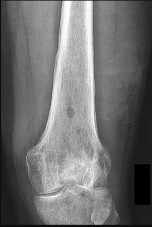

Figures 22a and 22b are the anteroposterior knee radiograph and an axial T2-weighted MR image of an 11-year-old boy who experienced knee pain following soccer practice. What is the best approach for biopsy?

The biopsy should cross only 1 compartment if possible and proceed as directly as possible to the tumor. The lateral parapatellar and medial parapatellar approaches cross the knee joint, potentially visualizing tumor into the knee. A direct anterior approach will contaminate an extensive portion of the quadriceps muscle and potentially complicate limb salvage. Biopsy should be performed at the institution at which definitive resection is planned.